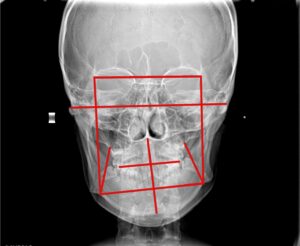

外科矯正治療前

理事長 萬 建一 歯科医師

歯学博士 / 一般社団法人日本歯科専門医機構認定 矯正歯科専門医 / 日本矯正歯科学会 認定医 / 日本成人矯正歯科学会 認定医・臨床指導医・総合指導医

院長 平田 彩子 歯科医師

日本矯正歯科学会 認定医 / 日本成人矯正歯科学会 認定医